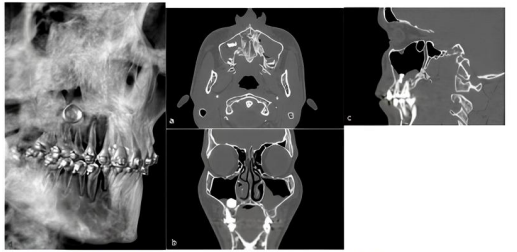

Homem, 18 anos, comparece ao serviço de cirurgia e traumatologia do hospital após

ter sido informado pelo seu ortodontista que havia um “corpo estranho” no seio maxilar direito. Ele

não relatava queixas inerentes à condição observada. Durante o exame clínico, o paciente relatou

que, há mais ou menos um ano, foi submetido à tentativa de extração do terceiro molar superior

direito sem sucesso, sem outras ou intercorrências no período. Ao exame físico extra e intraoral, não

foi observada nenhuma alteração digna de nota. Ao exame tomográfico, evidenciou-se uma área

hiperdensa na região referente ao seio maxilar direito com tamanho aproximado de 12 mm e

velamento deste, sugestivo da presença de conteúdo líquido a esclarecer em seu interior, e velamento

do seio contralateral.

Fonte: Agostinho, Santos e Araújo (2020).